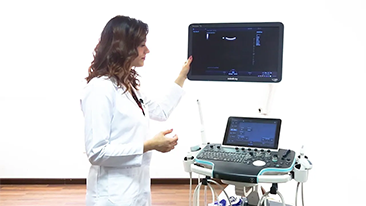

Mindray? ??? ??? ?? ??? ???? ??? ?? ??? ??? ????? ??? ????. ?? ???? ZONE Sonography? ??? ???? ?? Resona 7? ??? ZST+ ???? ?? ?? ? ?? ??? ????? ?? ??? ??? ??? ? ?? ????.

?? Resona 7? ???? ??? ?? ???? ??? ??? ???? ??? ?? ???? V Flow? ?? CNS ??? ?? 3D ??? ???? ?? ???? ?? ??? ?? ?? ?? ??? ??????. ???? ??? ??? ?? ?? ??? ??? ?? ?? ??? ??? Resona 7? ??? ???? ???? ??? ??? ??? ????.